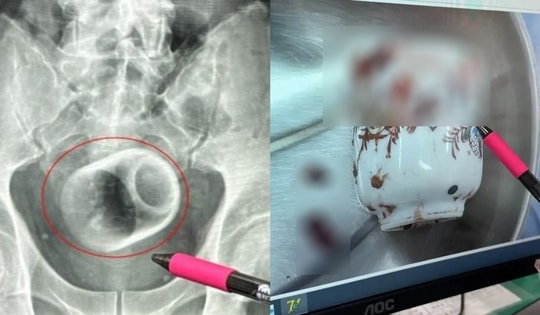

Người đàn ông bị chướng bụng, bác sĩ phát hiện ra bí mật đáng sợ